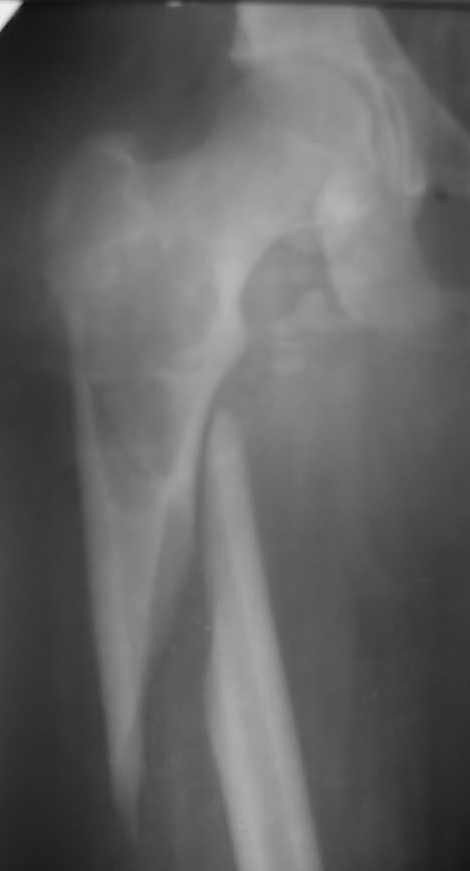

Патологический перелом бедренной кости.

Здравствуйте уважаемые коллеги ,Посоветуйте, пожалуйста, тактику лечения (метод фиксации) патологического перелома бедренной кости

у пациента 16- ти лет.С уважением.Ihor.

больше данных за кисту.наименьшее число рецидивов при лечении солитарной костной кисты дает интрамедуллярный остеосинтез.

Данный перелом надо расценивать как травматический, , перелом диафиза ниже солидной кисты, которая здесь является Р-логической находкой.

Оптимально БИОС с рассверливанием канала и зоны кисты. Срастется перелом и заодно полечите кисту.

Косая линия перелома говорит о травматическом характере. А СКК это сопутствующая находка. Если взглянуть на проблему с точки зрения онкологии, то дагноз ставиться на основании: клиники, рентгена, гистологии. Пренебрегать "золотым" правилом не допустимо, совет один - малоинвазивно трепанбиопсия.